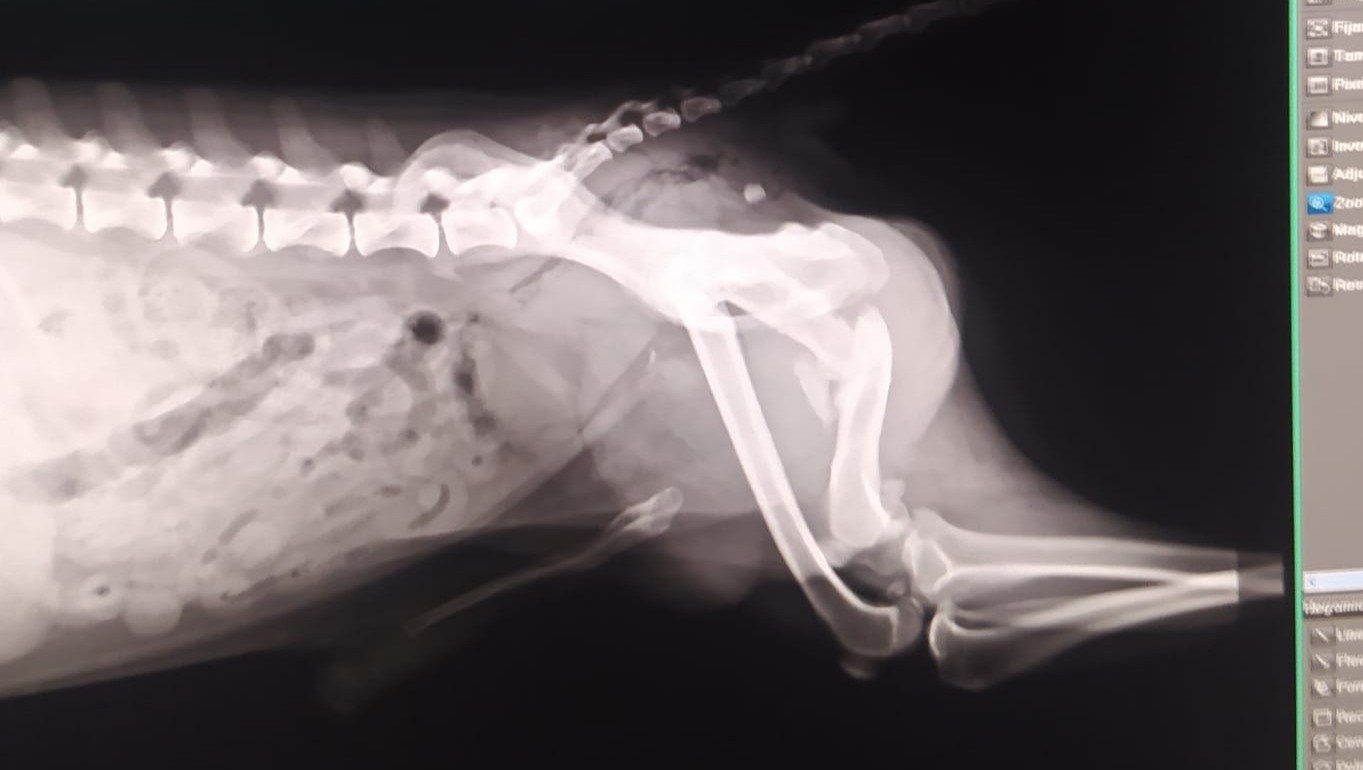

Su estado era lamentable, muy delgado, sucio, con un montón de nudos, cojeaba de una pata trasera y al cuello traía un mosquetón enorme.

Se llevó al veterinario no se localizó microchip y se le hizo una radiografía de la pata de la que cojeaba. Tenía una fractura antigua que no se había tratado debidamente, donde el hueso no había soldado, pero había generado una especie de "articulación", haciendo que su pata perdiese estabilidad y haciéndola completamente inútil.

Estas son las radiografías que se le hicieron tras la operación.